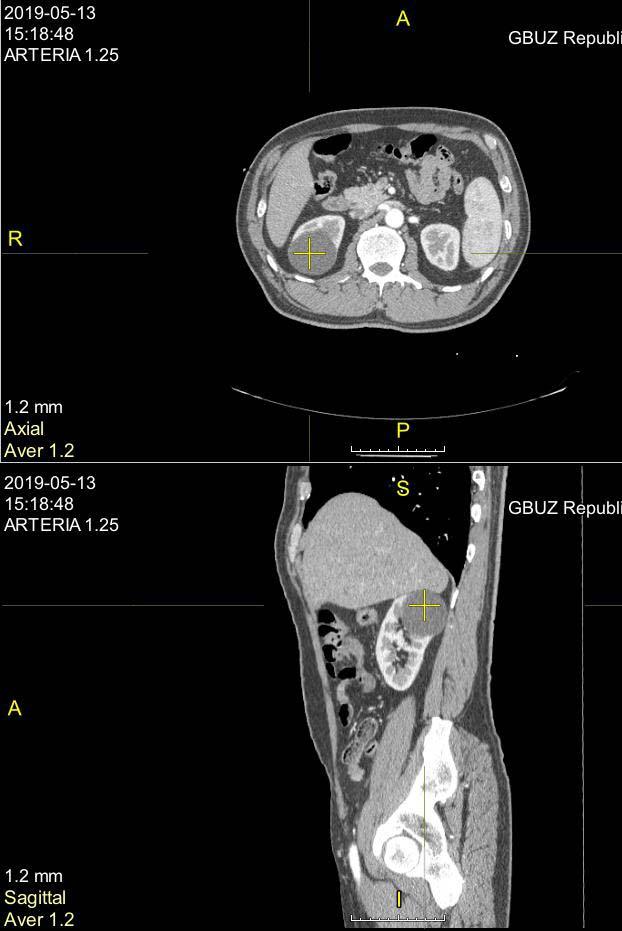

В конце прошлого года проходил УЗИ, там и обнаружилось новообразование, послали к урологу, потом в МОНИКИ к урологу, потом на КТ. В результате 16го февраля поставили диагноз - рак левой почки. Размер примерно 45мм. В понедельник 19 февраля были на приёме в МООД в Балашихе. Там подтвердили диагноз, и приговорили к удалению почки. На вопрос - можно ли сделать лапароскопическую операцию, нам ответили, что у него в брюшной полости скорее всего полно спаек (из-за перенесённого перитонита). Поэтому будут делать полноценную операцию, с доступом через забрюшинную полость. И удалять почку целиком, или возможно часть оставить, будут решать в процессе операции. Пока собираем анализы, консультируемся с кем можем, и ждём радиоизотопное исследование (назначено на 5 марта).

Ещё один момент - на второй почке киста 2,3см. Получается если одну почку удалят, вторая тоже не совсем здоровая.

Прилагаю сканы описаний УЗИ, КТ, выписку из приёма у местного уролога, анализ крови на ПСА, направление на радиоисследование в Балашихе. Есть ещё сам снимок КТ, но он на плёнке, отсканировать не получается.